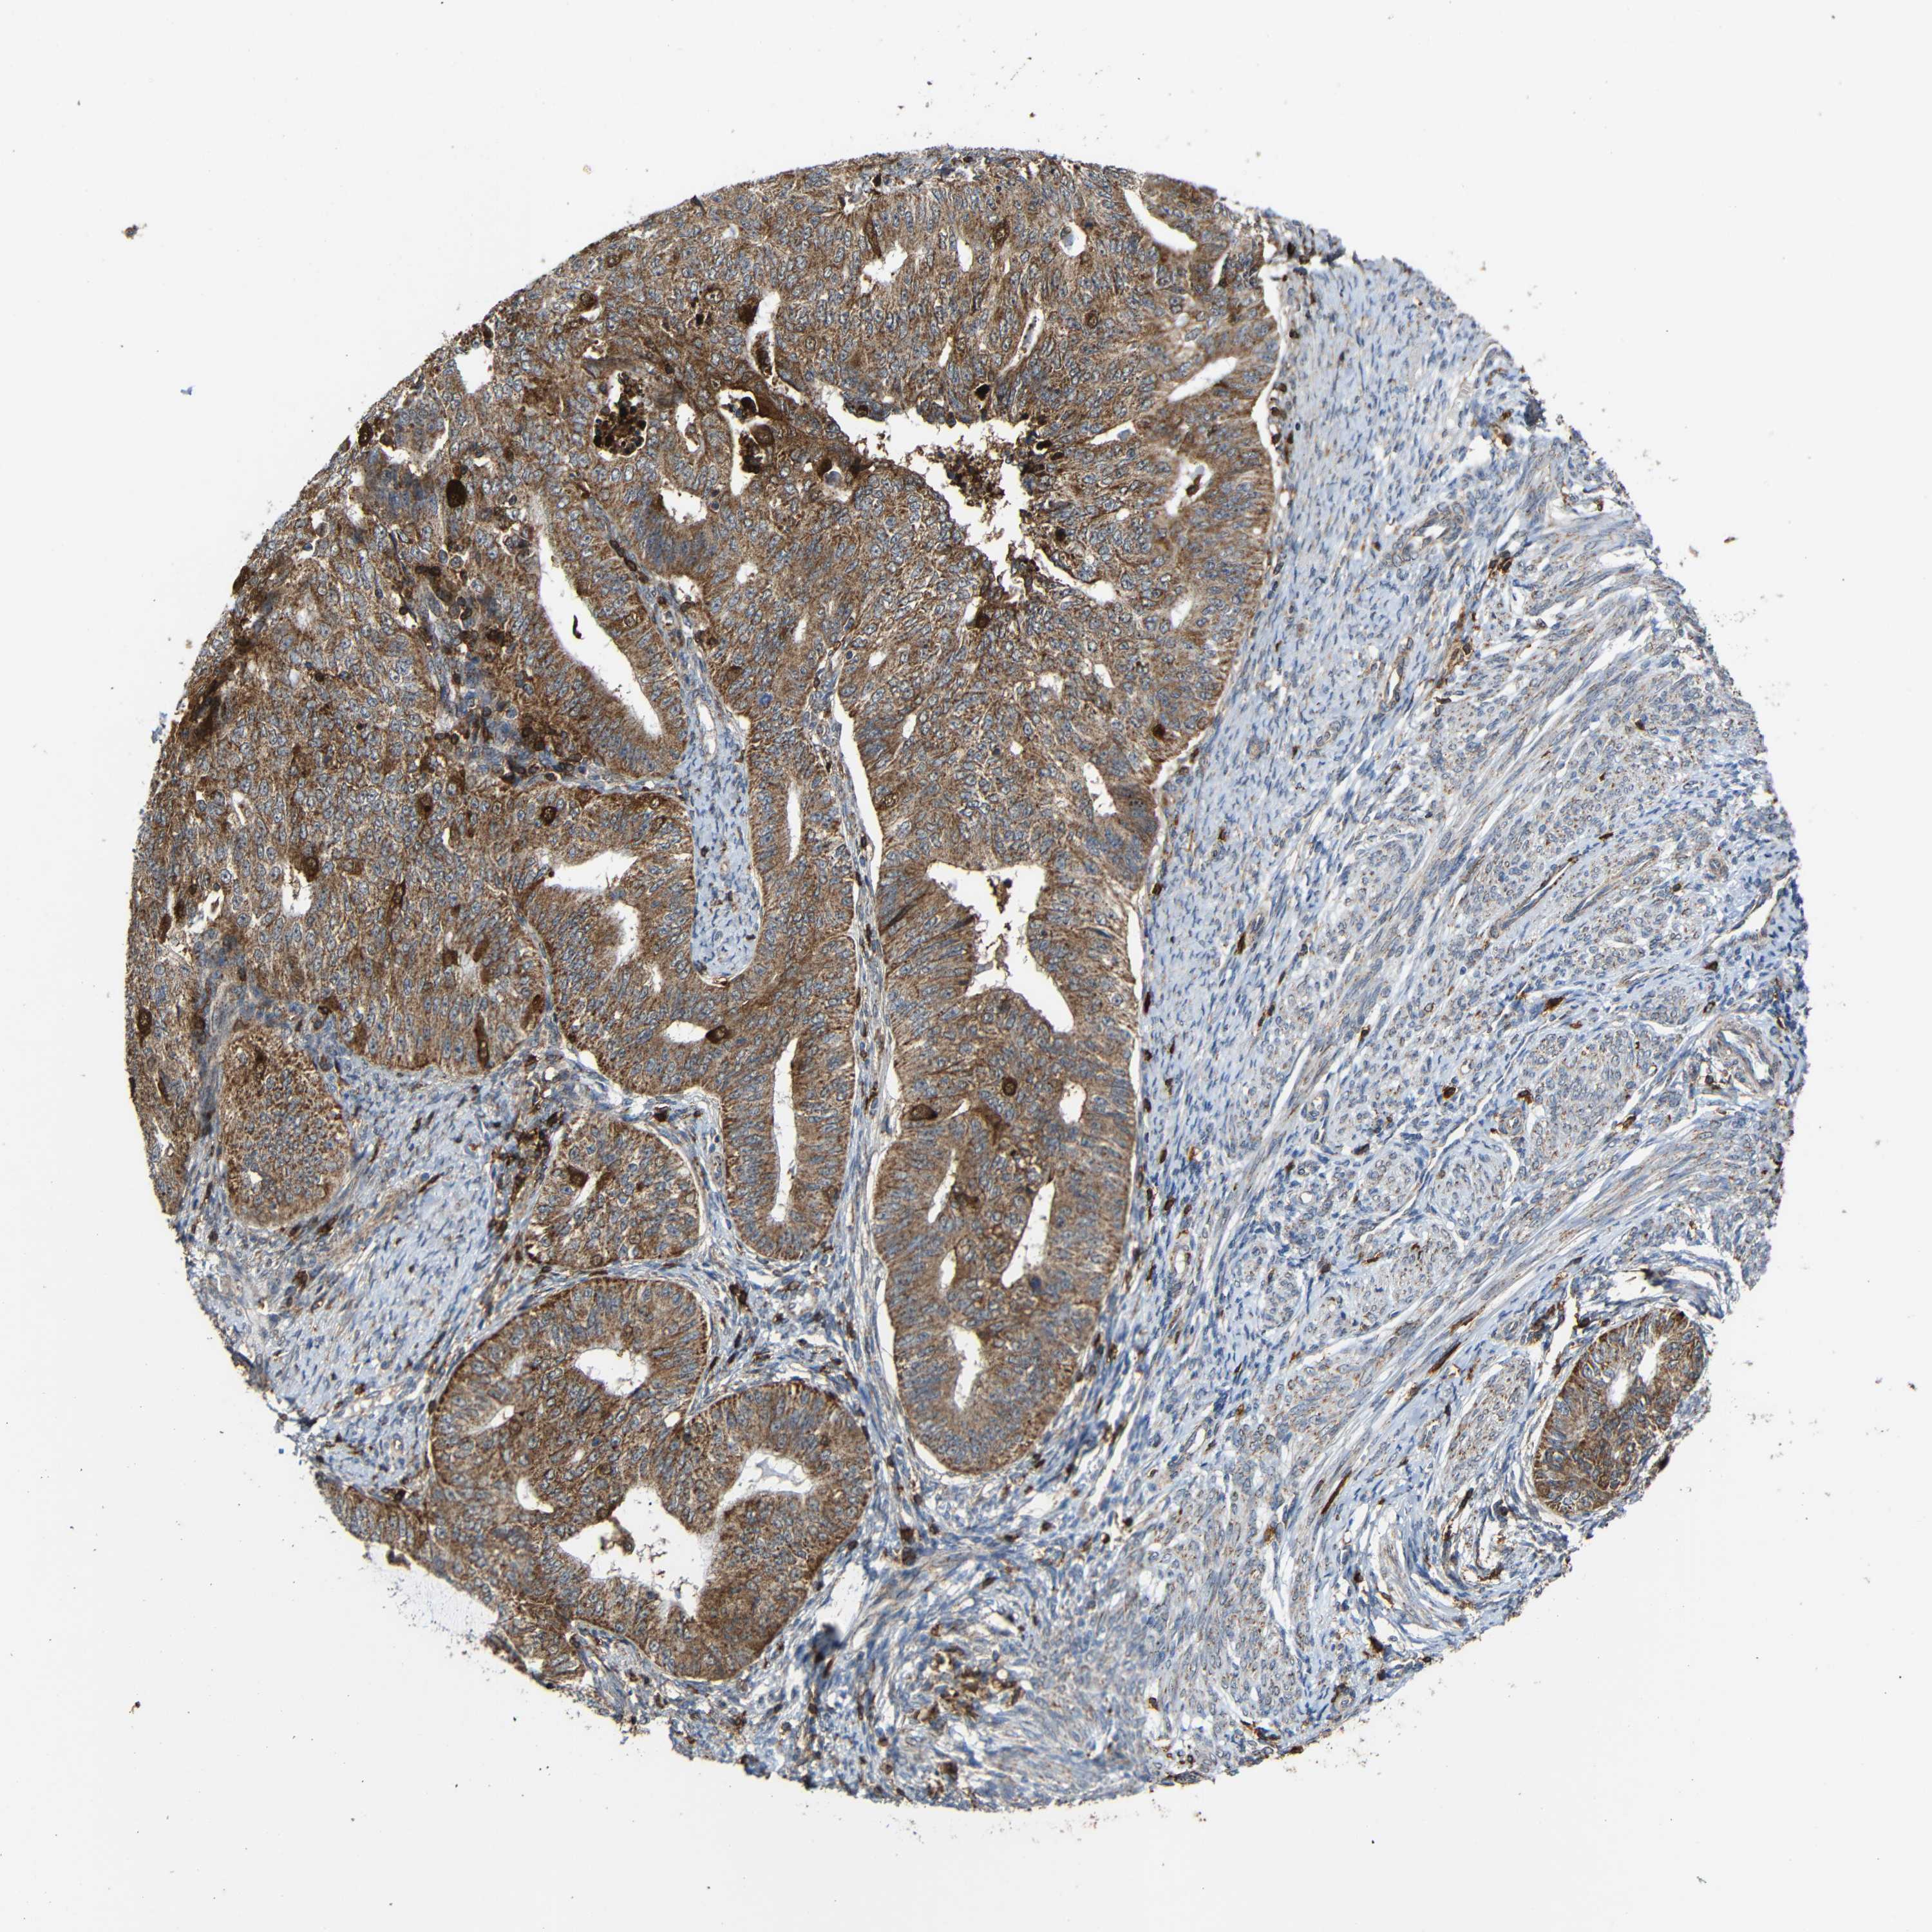

ENDOMETRIAL CANCER - Protein expressioni

A mouse-over function shows sample information and annotation data. Click on an image to view it in a full screen mode. Samples can be filtered based on level of antibody staining by selecting one or several of the following categories: high, medium, low and not detected. The assay and annotation is described here.

Note that samples used for immunohistochemistry by the Human Protein Atlas do not correspond to samples in the TCGA dataset.

Antibody stainingi

Antibody staining in the annotated cell types in the current human tissue is reported as not detected, low, medium, or high, based on conventional immunohistochemistry profiling in selected tissues. This score is based on the combination of the staining intensity and fraction of stained cells.

Each image is clickable and will lead to virtual microscopy that enables deeper exploration of all samples and also displays staining intensity scores, fraction scores and subcellular localization as well as patient and tissue information for each sample.

Antibody HPA011294

Antibody HPA012819

Staining

High

Medium

Low

Not detected

Intensity

Strong

Moderate

Weak

Negative

Quantity

>75%

75%-25%

<25%

None

Location

Nuclear

Cytoplasmic/membranous

Cytoplasmic/membranous,nuclear

Adenocarcinoma, NOS